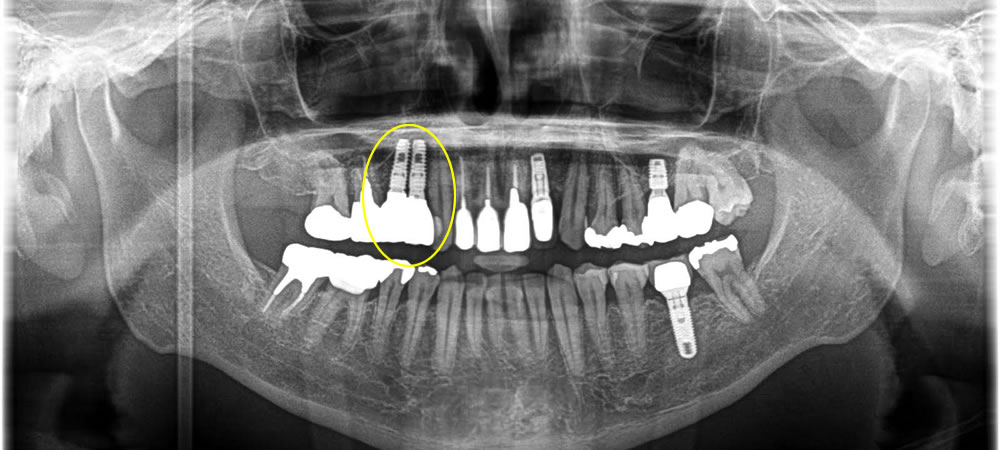

上部構造の装着・治療完了

初期固定を取ることができていたので、3週間後に糸を取ってそこから3ヵ月待ち、骨とインプラント体がオステオインテグレーションしている事を確認し、上部に歯を作成していきました。

結果、物を噛む事ができ、食事がしやすくなったと満足して頂く事ができました。6年経過後も歯茎の下がりもなく綺麗な状態を保っています。